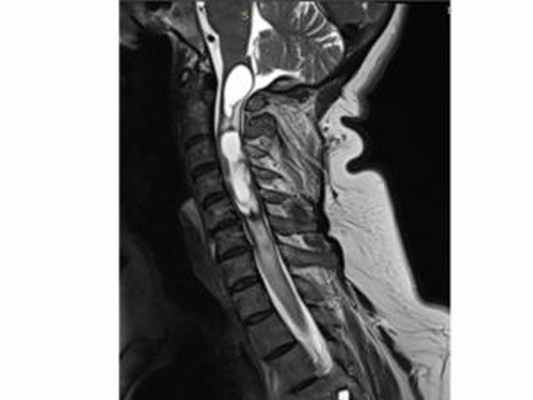

МРТ изображение (T2-взвешенное изображение) шейного отдела спинного мозга. Определяется сирингомиелия и сирингобульбия на фоне интрамедуллярной опухоли спинного мозга на уровне С2-С4.